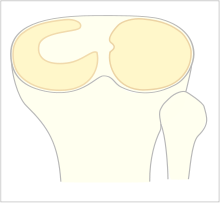

The Watanabe classification of discoid lateral meniscus is: (A) Incomplete, (B) Complete, and C) Wrisberg-ligament variant [2] Normally, the meniscus is a thin crescent-shaped piece of cartilage that lies between the weight bearing joint surfaces of the femur and the tibia. It is attached to the lining of the knee joint along its periphery and serves to absorb about a third of the impact load that the joint cartilage surface sees and also provides some degree of stabilization for the knee. There are two menisci in the knee joint, the outside one being the lateral meniscus the inner one the medial meniscus. A discoid meniscus is a congenital anomaly of the knee found in 3% of the population (up to 15% in Asia). It typically affects the lateral meniscus and may be found bilaterally (20%). Instead of the narrow crescent shape, as seen in a normal meniscus above, a discoid meniscus is thickened, and has a fuller crescent shape. In addition, a discoid meniscus does not taper as much towards the center of the joint and is shaped like a disc. The thickness of the meniscus, its diminished vascular blood supply, and in some instances, weak capsular attachment, makes it more prone to tears compared to a normal meniscus. The anomaly in itself is asymptomatic; however, a tear of the meniscus can result in pain, swelling, and snapping of the affected knee. The orthopedic classification of discoid menisci includes: complete, incomplete or Wrisberg-ligament types as depicted here. Coverage of the lateral tibial plateau determines the designation of complete or incomplete. The Wrisberg-ligament type has an abnormal posterior attachment by attaching to part of the posterior cruciate ligament.